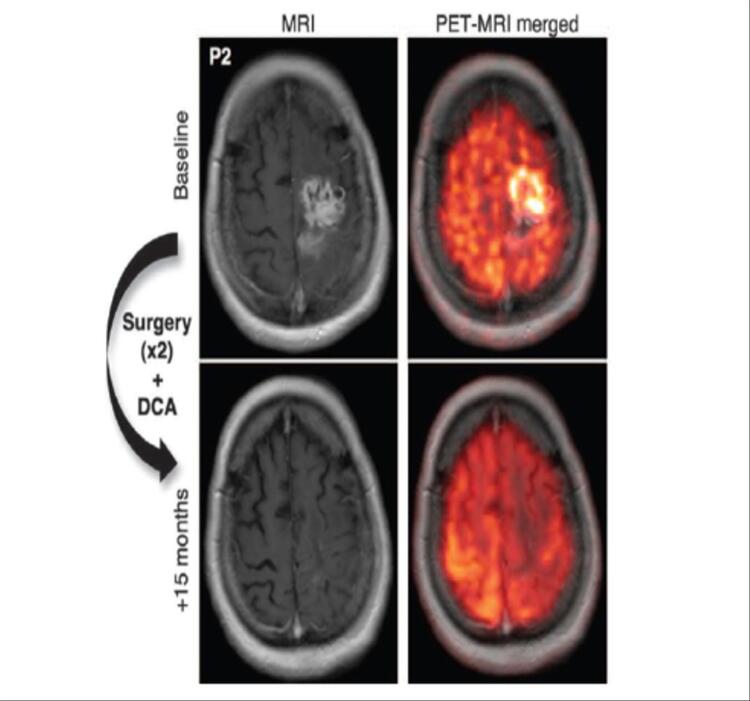

MRI Scan showing tumour regression

After 15 months of treatment with oral DCA as the only therapeutic agent, apparent resolution of the tumour is seen in patient #2 (P2) from published clinical trial.